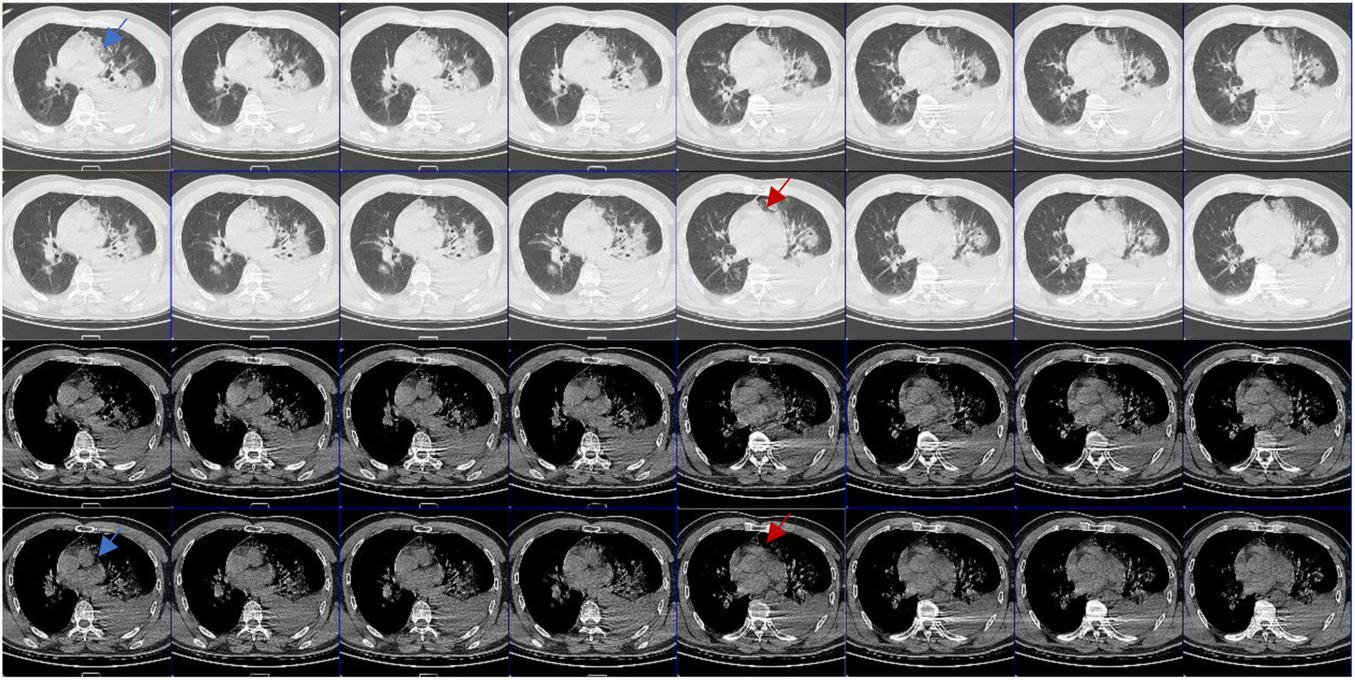

FIGURE 4

Computed tomography (CT) images in different window settings: As the blue arrow shows, there is no obvious pericardial structure in the left area of pulmonary artery, which is closely related to lung tissue and has irregular edge; as the red arrow shows, there is an abnormal notch near the pulmonary artery, which is rare when the pericardium is intact.

Congenital absence of pericardium is often difficult to diagnose, and it has no specific symptoms and signs, so it is often ignored. CAP has certain imaging diagnostic features (6, 7): (1) pulmonary parenchyma between the main pulmonary artery and the ascending aorta; (2) pulmonary parenchyma between the base of the heart and the left diaphragmatic muscle; (3) pulmonary parenchyma between the ascending main aorta and the right pulmonary artery; (4) “SNOOPY” sign on chest radiograph. Even so, it is still very difficult to clinically diagnose CAP. Sergio et al. (6), reviewed the imaging examinations of 12,888 patients and found only 1 case with partial pericardial defect (left heart) with conditions (1) and (2), and 10 cases with false positive results. Reviewing the radiographic findings of this patient after the injury, we did find some evidence of CAP (see Figure 4), but did not find any obvious radiographic features in accordance with the literature.

Computed tomography and magnetic resonance imaging (MRI) are the gold standard for the diagnosis of CAP (7), but it is still difficult to make a diagnosis in the absence of symptoms and experience, so that in many cases the diagnosis is made during surgeries. In this case, CAP was missed by CT. Due to severe lung contusion, the patient was dependent on ventilator support. We didn’t have the opportunity to perform MRI or any other examinations.